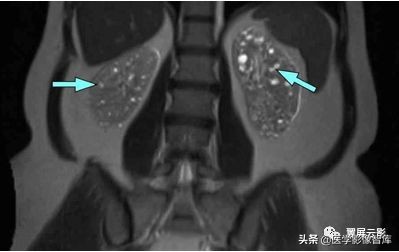

多囊肾

本病常合并多囊肝,此为先天性常染色体显性遗传性疾病,多数学者认为多囊肝是在多囊肾的基础上基因突变的结果,并定位于16号染色体上,也有学者认为该病是由于胚胎发育不良所导致,于胚胎早期管道形成时排列失常,导致无数迷管,于胚胎晚期未退化,且逐渐扩张成囊,成多发性囊肿病,根据发病年龄的不同,将其分为儿童型和成人型,本病多发生于双侧肾脏,可继发感染,结石以及囊内出血和囊壁钙化,也可以恶变,并有阻塞性黄疸及合并皮下囊肿的报道,临床上早期无症状,就诊时肾脏功能已经不同程度受损,肝功能受损程度较轻。

MRI表现为双肾增大和分叶状轮廓,多发囊肿多数为长T1长T2信号,出血性囊肿可为短T1长T2信号或长T1短T2信号,增强扫描所有病灶均不强化,应同时观察合并的多囊肝及胰脾多发囊肿。